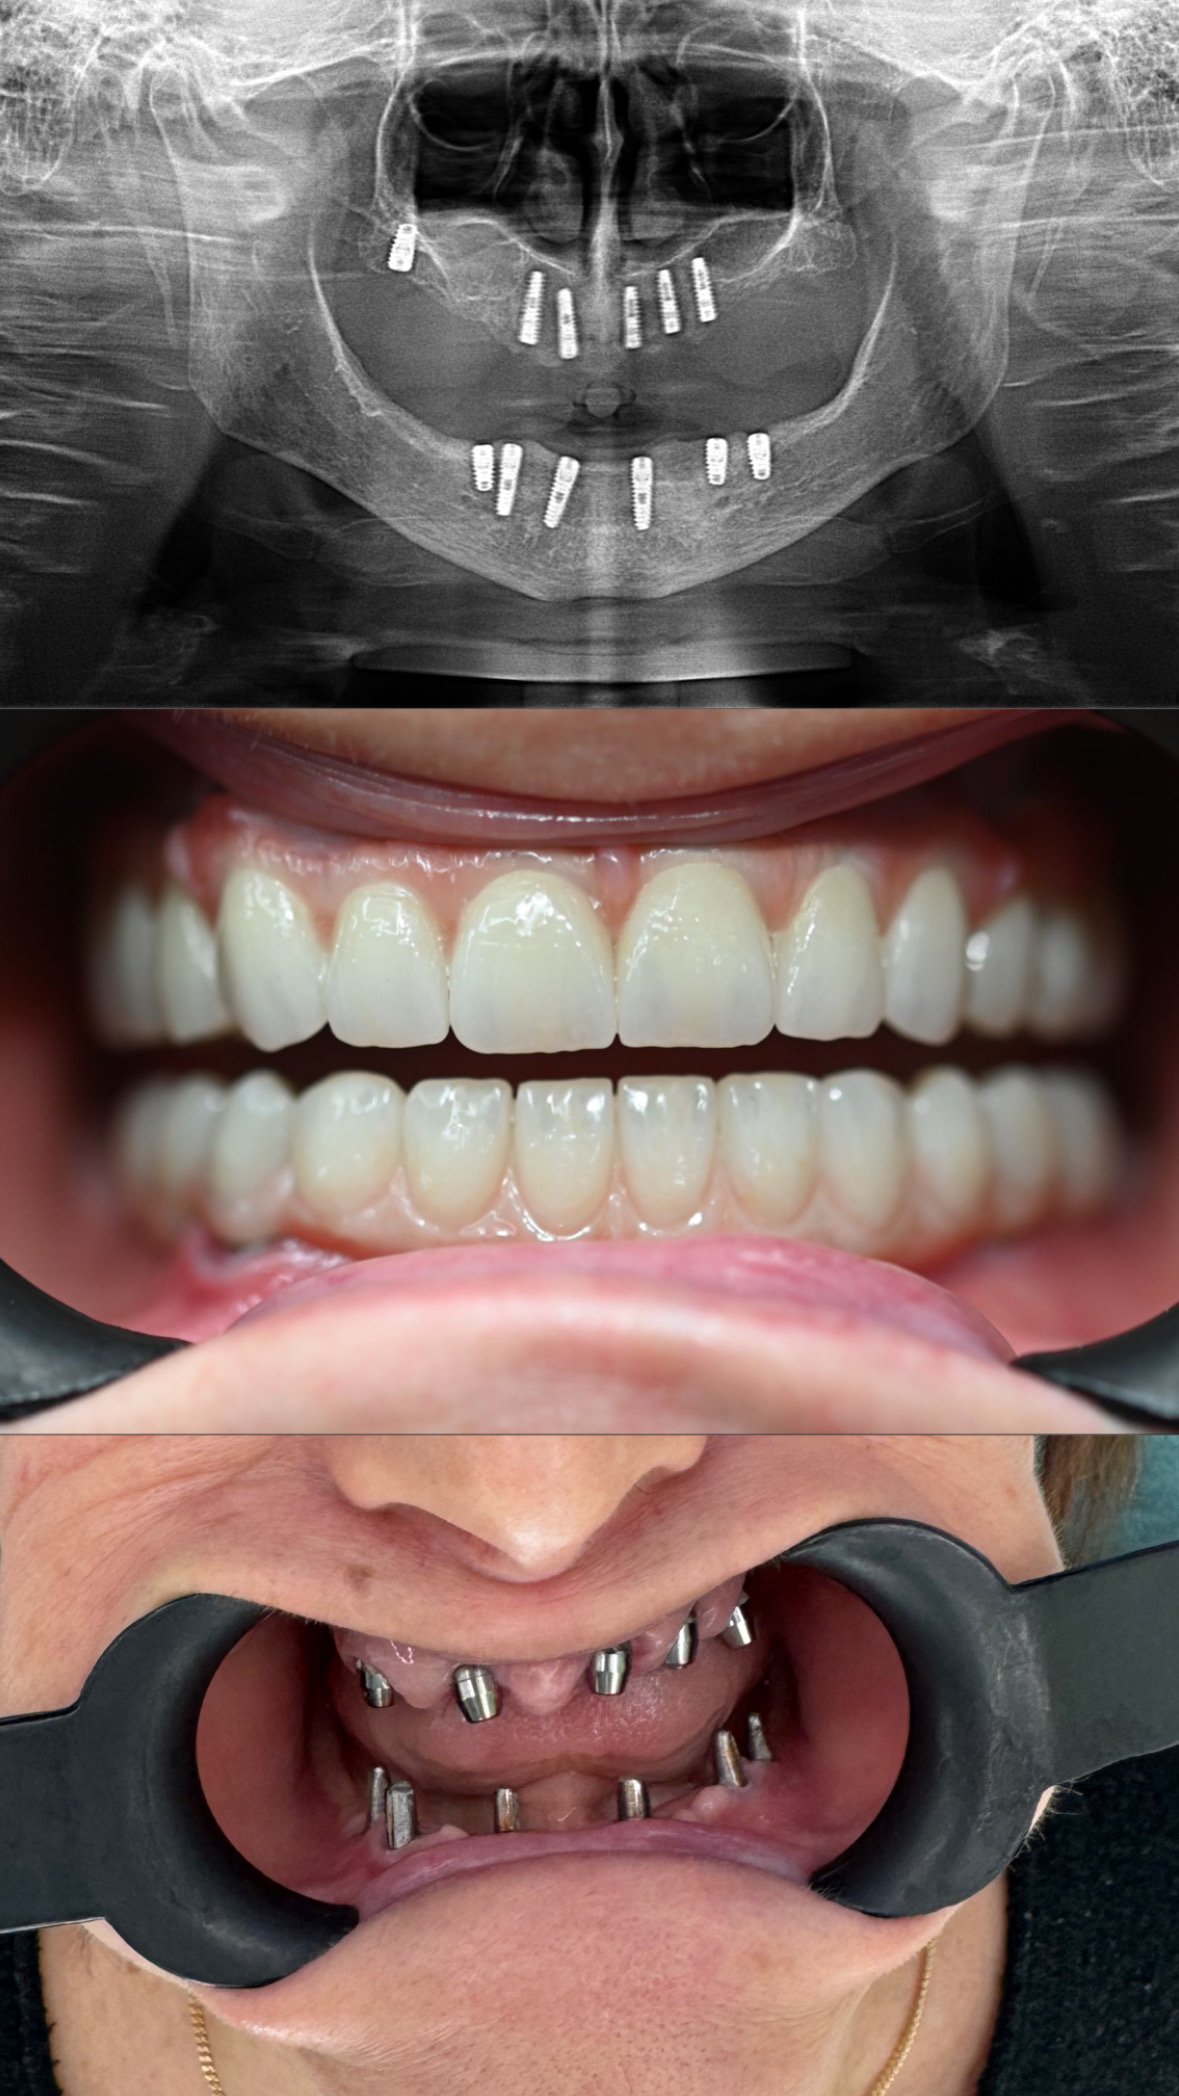

Lavori

Nuove idee

per un sorriso più sano